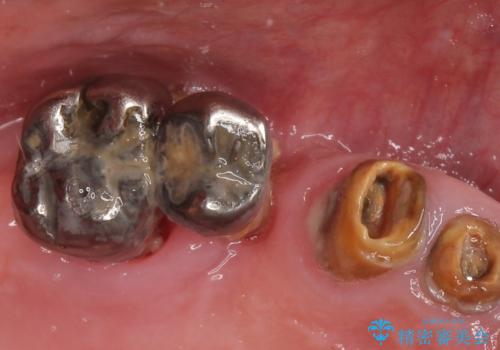

- 歯がぐらぐらで咬めないことを主訴に来院された患者様です。

他院では上顎骨が薄いためインプラントできないと言われたとのことでした。

精査したところ、歯周病に罹患した歯を長年放置したことから骨吸収が進行し、上顎骨の厚みはとても薄くなっていました。